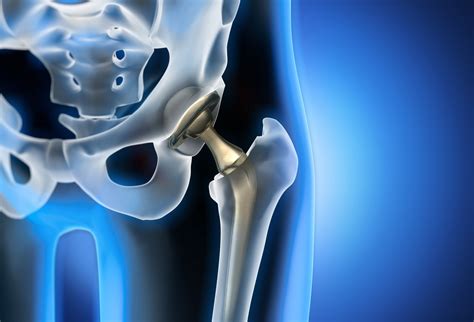

Modern surgical techniques have significantly advanced, making hip replacement one of the most successful orthopedic procedures. While the idea of surgery can be daunting, the primary goal of the procedure is to relieve pain and improve your ability to function. After surgery, patients typically begin physical therapy almost immediately, focusing on strengthening the muscles around the new joint to support long-term stability and mobility.